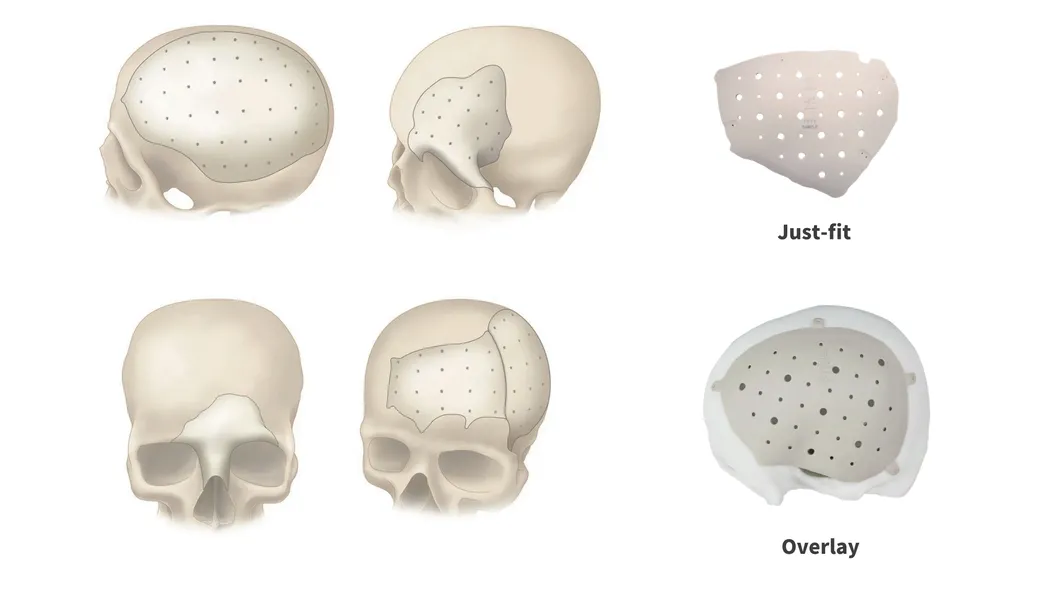

PEEK can be designed and provided in single or multiple pieces with just-fit or over-lay concept as indicated above. Additionally, this patient specific implant can be reliably fixated using cranial fixation systems.

Perfect Contour Reconstruction

Precisely match the natural contour and convenient to implant. CAD/CAM technology allows to restore the defect models and reconstruct the natural contour of the brain.